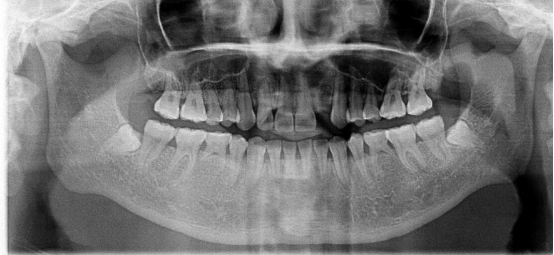

不連續(xù)性牙缺失修復案例

53歲的周女士家住福州晉安,由于患有嚴重的牙周炎導致牙齒沒剩下幾顆了。

“這邊缺一顆,那邊缺幾顆,這咬東西也太不得勁了,有牙齒跟沒牙齒一樣。”周女士深知牙齒缺失的痛苦,但是卻因為經濟的原因一直拖延沒有進行牙齒修復:“做牙齒多貴了,一顆就幾萬塊哪里舍的?!?

錢雖然重要但缺失牙確實痛苦。而近期周女士又湊巧在報紙上看到科爾口腔的“敬業(yè)?!惫婊顒拥南ⅲ活w牙齒可以免費領取4000元的種植牙紅包,優(yōu)惠力度之大前所未有,種植5顆還可以省下幾萬塊。

周女士來院與劉斌元教授進行交流后,劉斌元教授表示:“周女士缺失的牙齒是非連續(xù)性的,因此要種上好幾顆。牙齒缺失千萬不可掉以輕心,長時間缺失牙齒可造成牙槽骨萎縮,還會影響相鄰牙齒健康狀況”